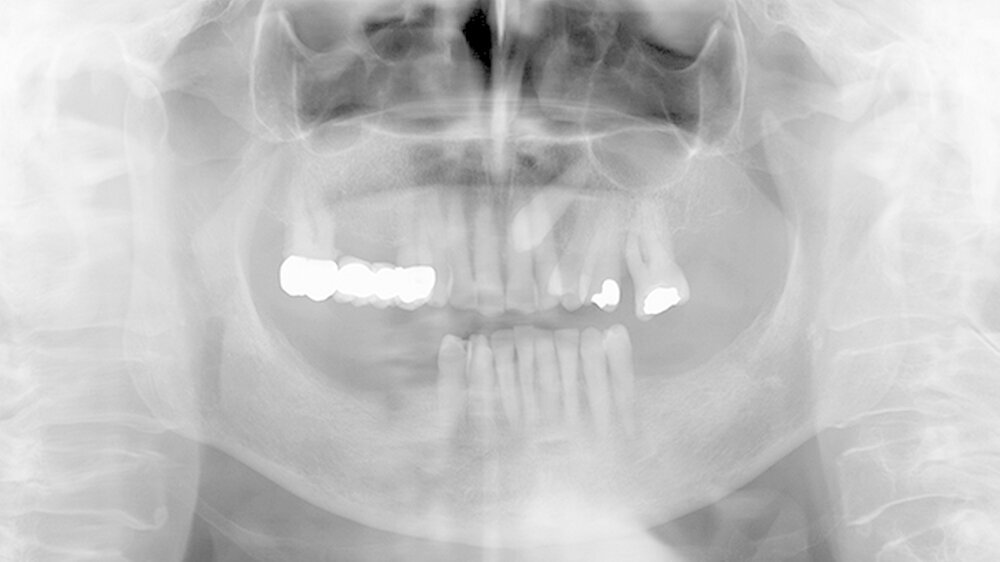

Eine Woche nach Abschluss der internistischen Therapie stellte sich die Patientin zur Verlaufskontrolle in unserer Klinik vor, dabei zeigte sich eine vollständige Remission der hyperplastischen Gingiva bei weiterhin insuffizienter Mundhygiene (Abbildungen 4 und 5).